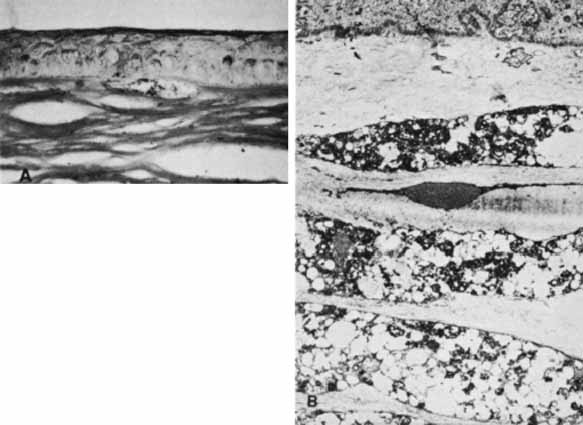

Fig. 9 Histopathology of healed tears in Descemet's membrane from congenital glaucoma. A. Regenerating corneal endothelium has produced new basement membrane in the bed of the tear and over each edge (arrows) of the tear. B. Main figure demonstrates one edge of the tear in Descemet's membrane, which has separated from the overlying stroma and coiled anteriorly like a watch spring. Regenerated basement membrane has encased this and formed a prominent ledge. Inset. Other edge of the tear, in which regenerated basement membrane forms a ridge protruding into the anterior chamber. (Waring GO, Laibson PR, Rodrigues MM: Clinical and pathologic alterations of Descemet's membrane: With emphasis on endothelial metaplasia. Surv Ophthalmol 18:325, 1974)

Histopathologically, the edge of a Descemet tear curls toward the stroma, possibly because of the differential elasticity between the anterior banded and posterior nonbanded layers within Descemet's membrane.67 As the new regenerating endothelium spreads over the edge, it encases the original coiled Descemet's membrane in a thick multilaminar periodic acid-Schiff (PAS)-positive basement membrane (Fig. 9). This new basement membrane forms the clinically evident refractile edge. Within the bed of the tear, the regenerating endothelium lays down an irregular basement membrane with focal excrescences that produce the beaten-metal appearance.